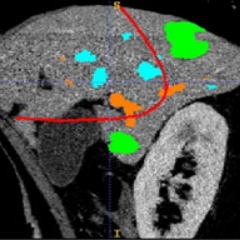

Risk maps for liver surgery (2013)

Intra-operative display of risk areas